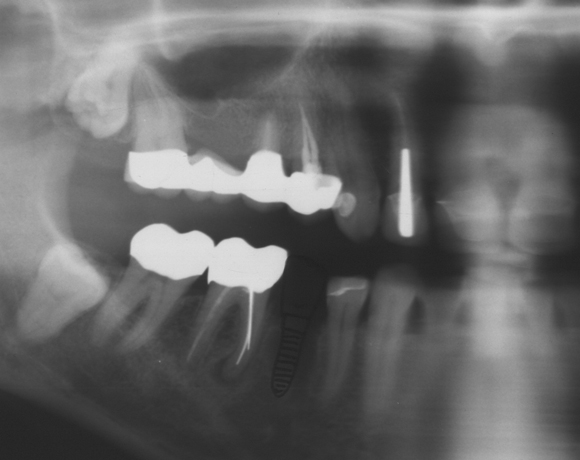

Ein Projekt aus dem Jahr 2013

Bei diesem Patientenfall wird die offene Abdrucknahme gezeigt und die Herstellung einer Krone auf einen CAD/CAM Pfosten.